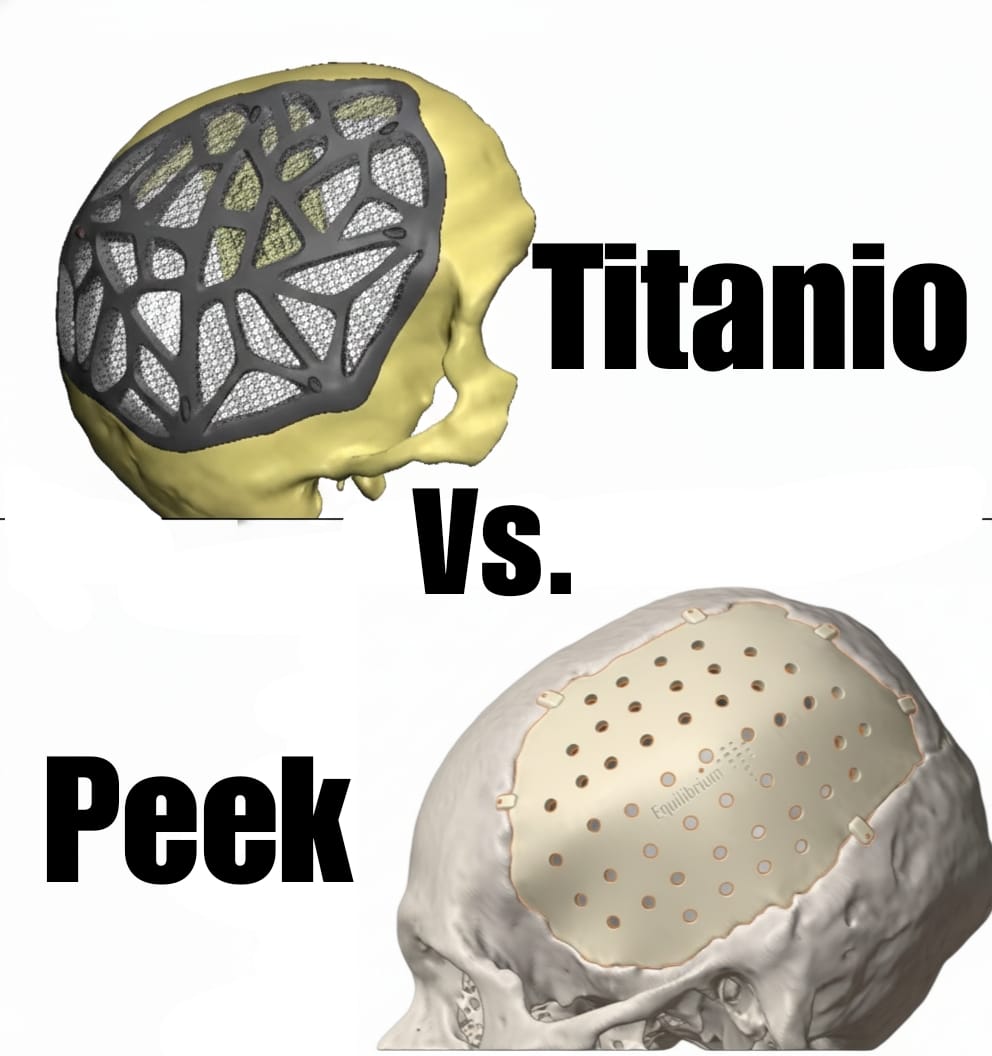

Variedad de Materiales

La prótesis personalizada puede fabricarse en diferentes materiales, seleccionados según el uso clínico, la región anatómica, las dimensiones del implante y los requerimientos específicos del cirujano. Cada caso es evaluado de manera individual para garantizar seguridad, funcionalidad y durabilidad.

-

Materiales Biocompatibles

Fabricamos implantes en titanio, cromo cobalto, PMMA, cerámica bifásica, hidroxiapatita y PEEK, todos seleccionados según la indicación médica y el tipo de procedimiento quirúrgico.

Titanio Trabecular

Reproducimos en nuestros implantes de titanio trabecular biocompatible la misma trama de cavidades que posee el hueso humano, logrando implantes livianos, altamente resistentes y con excelente integración ósea.